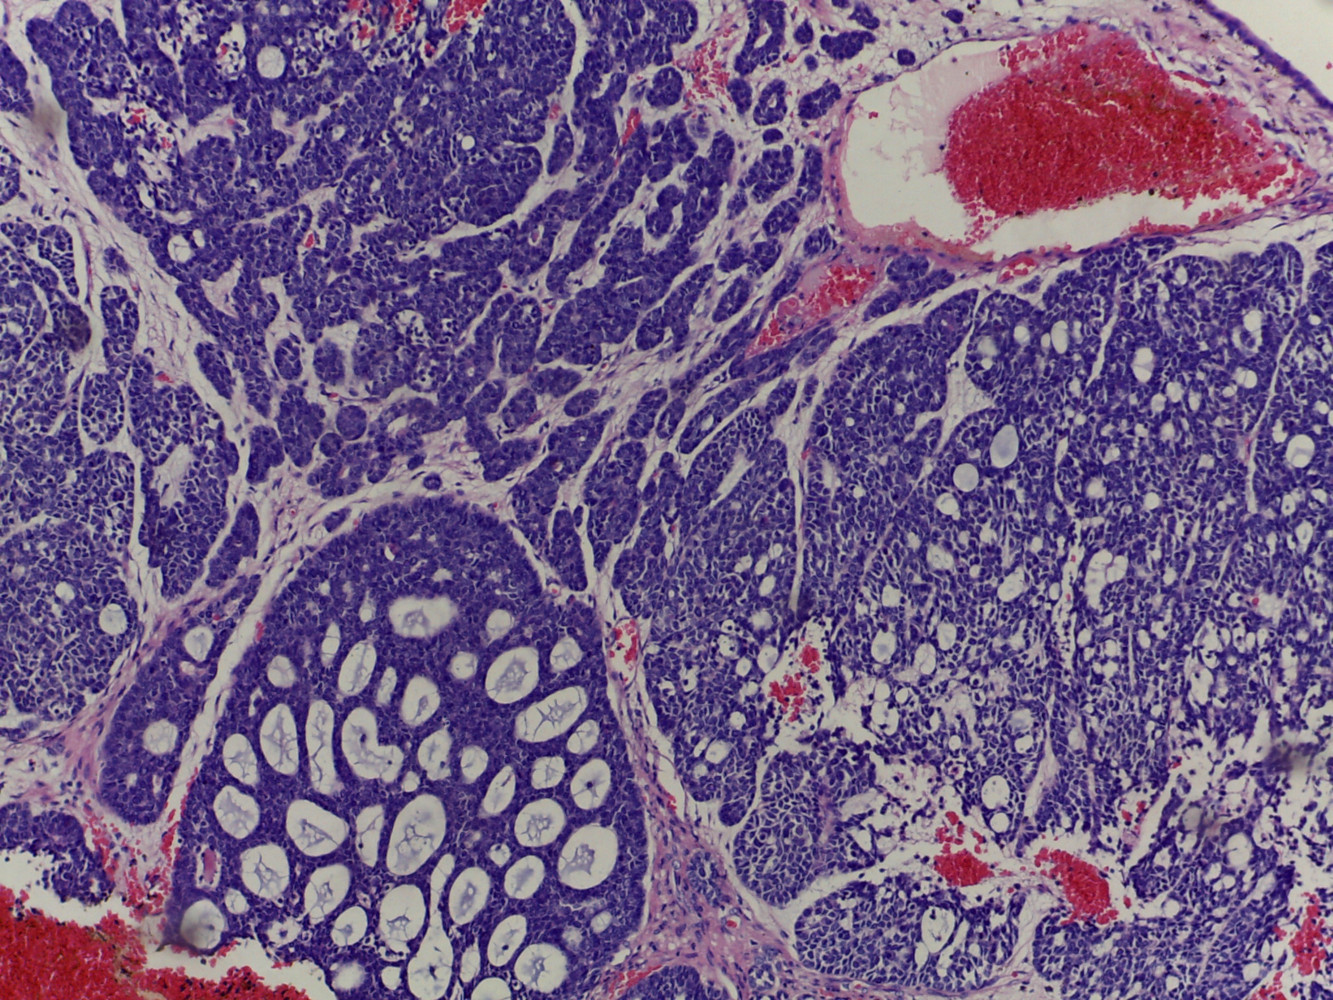

Diagnóstico: Carcinoma multifenotipico sinonasal asociado a VPH

Comentario: Anteriormente conocido como carcinoma con características semejantes al carcinoma adenoideo quístico asociado a VPH, este carcinoma se ha descrito hasta ahora solamente en tracto sinonasal, tiene características histológicas semejantes al carcinoma adenoideo quístico con componente cribiforme y tubular y un componente de carcinoma epidermoide in situ en el epitelio superficial . Todos los casos descritos están asociados a infección por VPH .